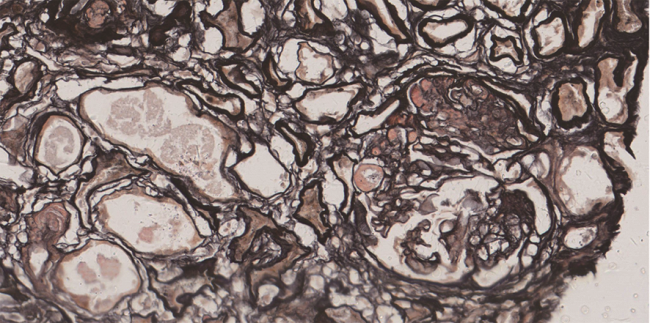

GVHD的发生及演变(图2):HSCT后28 d,患者出现纳差,肝功能总胆红素24.4 μmol/L,碱性磷酸酶355 U/L,谷丙转氨酶116 U/L,考虑急性GVHD肝损害(肝炎型),予调整CsA剂量(图1)联合MP免疫抑制等治疗后病情好转。HSCT后5个月MP、CsA完全停服,6个月患者再次出现纳差、黄疸,总胆红素最高升至57.3 μmol/L,查肝胆彩超未见肝肿大、胆道扩张及梗阻,不支持肝静脉闭塞性疾病,仍考虑急性GVHD肝损害,再次予强化免疫抑制治疗后好转。1年余患者出现口腔溃疡、皮肤疱疹,伴水肿、尿蛋白3+、血白蛋白23 g/L,血肌酐正常,考虑慢性GVHD累及口腔黏膜和皮肤、HSCT后肾病综合征,停用CsA,改为他克莫司,联合MP免疫抑制治疗后症状改善。3年余患者出现全身皮肤呈白癜风样改变,趾甲如病甲改变(图3)。4年余患者水肿、蛋白尿加重,血肌酐升至293 μmol/L,肾活检病理提示GVHD相关的膜性肾病、肾小管间质病变较重(不排除合并慢性肾小管间质性肾炎可能,图4),遂停用他克莫司,改为MMF联合MP免疫抑制治疗。同年血肌酐升至722 μmol/L,进入腹膜透析治疗。9年余患者气促,先后2次胸部CT提示单侧(右)胸腔中-大量积液,胸水检查排除感染及肿瘤,结合患者无右颈内静脉置管病史,无上腔静脉阻塞体征,考虑为GVHD浆膜积液可能,予引流等对症并加用MP治疗后胸腔积液未再复发。此外,HSCT后2年始患者反复出现腹痛、排血性水样便,每次均在予MP免疫抑制治疗后好转,考虑为急性GVHD胃肠道受累。近1年来患者再次发作性血性水样便(图5),胃管引流出血性液体,胃镜(图6)及全腹部CT平扫未见明确占位病变等(图7),不排除胃肠道GVHD症状,经抑酸、护胃等对症治疗后好转。自此截至2022年5月,患者未再使用糖皮质激素及免疫抑制剂,目前处于维持性血液透析、长生存状态。

注:肾活检仅穿刺到1条肾组织,光镜提示以髓质为主,仅见1个硬化的肾小球。予冰冻荧光组织石蜡包埋后再次制片(PASM ×200):共见4个肾小球,其中3个球性硬化,1个节段硬化,残存球袢基底膜增厚伴上皮下嗜复红物沉积,可疑钉突形成。肾小管上皮细胞颗粒变性及空泡变性,多灶性及小片状小管萎缩(约60%),部分小管代偿性肥大,管腔扩张。肾间质多灶性及小片状纤维化伴小灶单个核细胞浸润,小动脉及细动脉结构尚好。免疫荧光:6个肾小球中3个球性硬化。IgG+~++(IgG1+、IgG4±),C3+,κ(±)、λ(±)弥漫性球性分布,颗粒状沉积于毛细血管壁;IgA、IgM、C1q、纤维蛋白原、IgG2、IgG3及磷脂酶A2受体均阴性。刚果红染色(-)